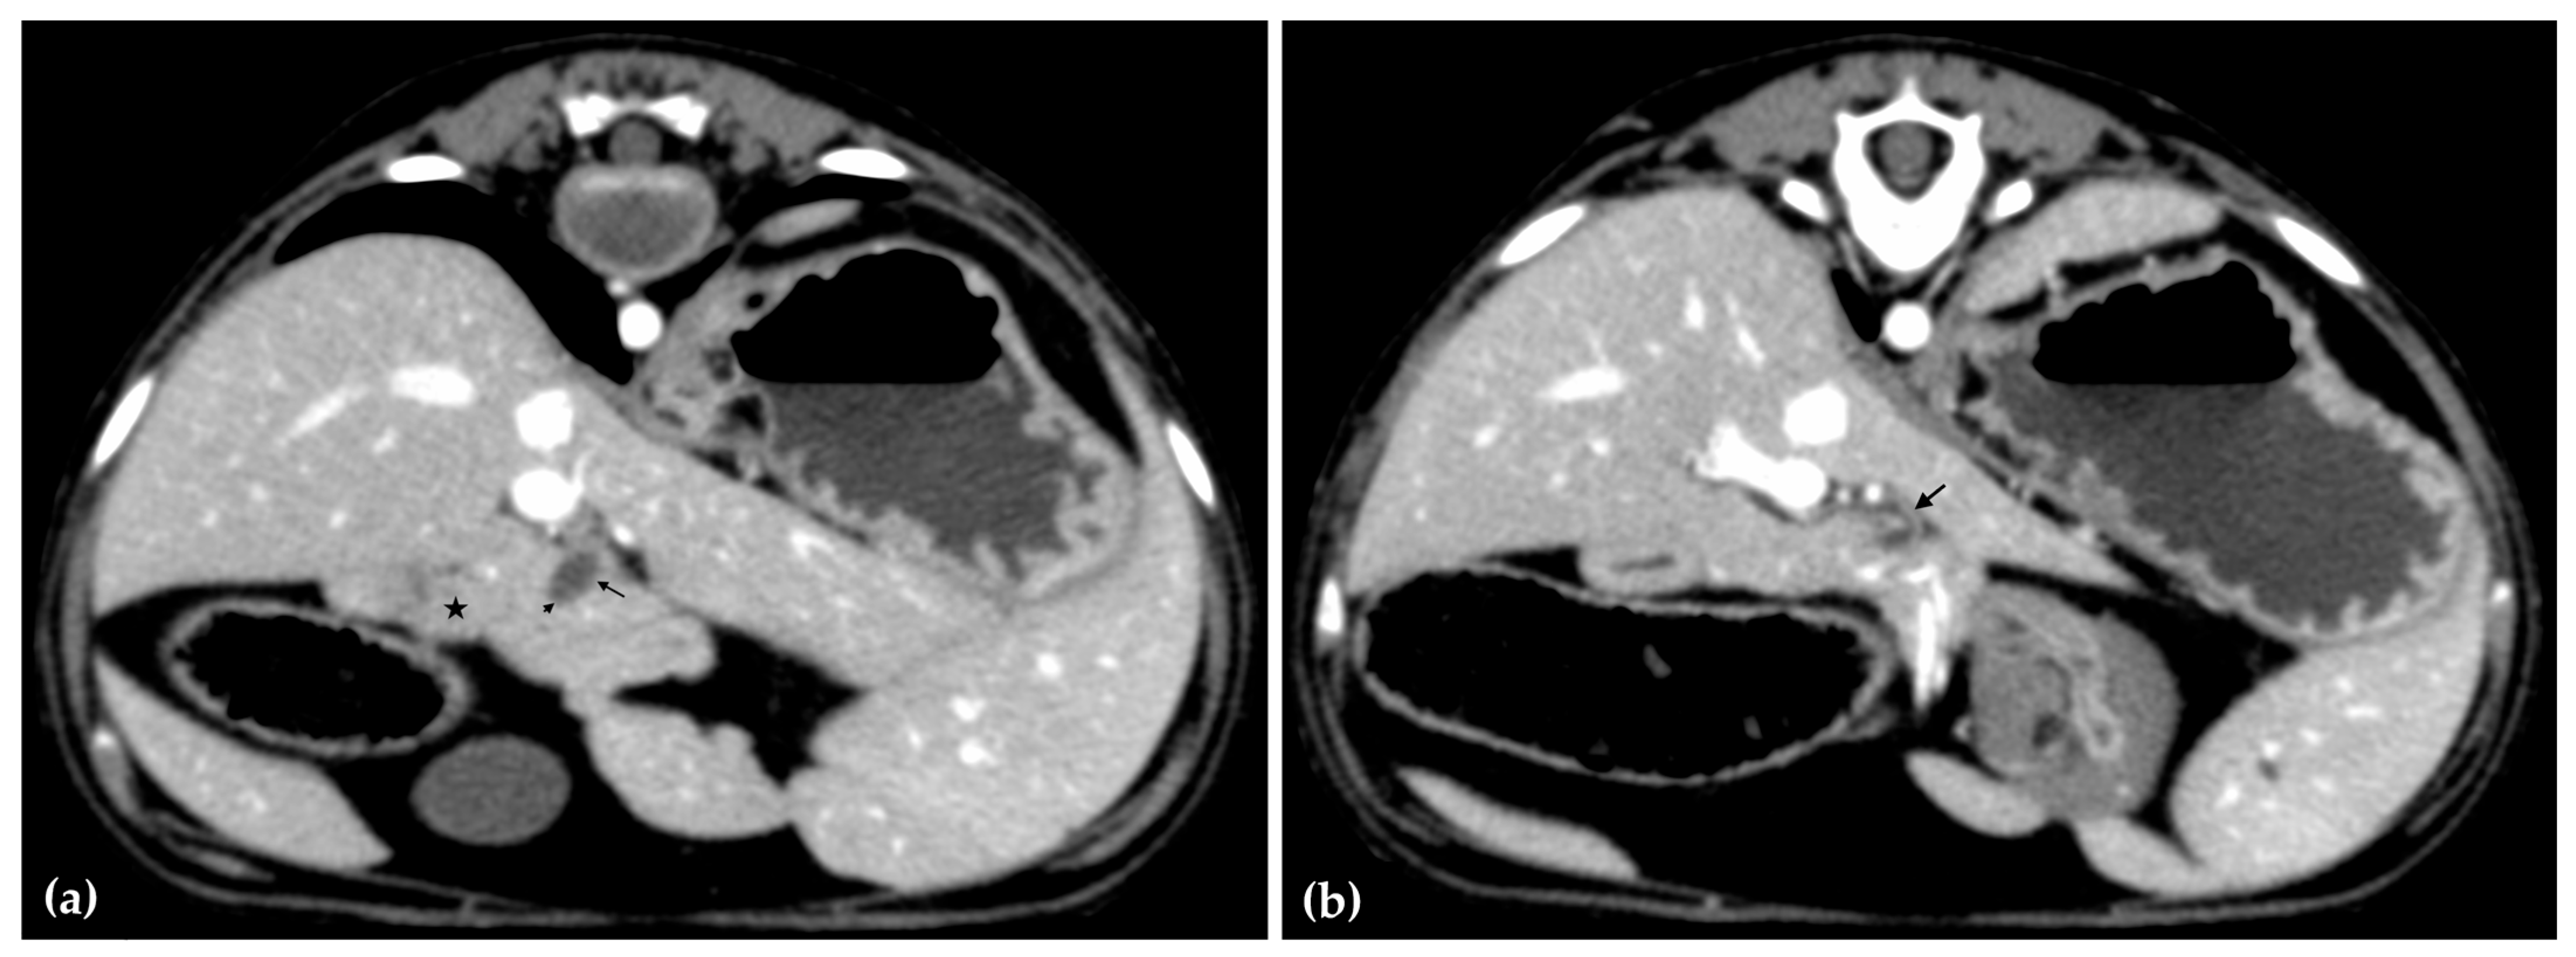

The patient was positioned in sternal recumbency. Helical scans of the abdomen using a multidetector CT were obtained with pre-contrast, post-contrast arterial, portal, and delayed images, all in a soft tissue reconstruction kernel (acquisition parameters: Slice thickness 0.9 mm, pitch 0.8, tube rotation time 0.5 s, 412 mA, 120 kVp, 512 × 512 matrix; Philips Brilliance-40, Philips International B.V., Amsterdam, Netherlands). Prior to contrast administration, the gallbladder was noted to be filled with predominantly mildly hyperattenuating (av. 25 HU) fluid. Dilation of the distal left intrahepatic biliary ducts were again seen (Figure 3a). Following intravenous contrast administration (Optiray 350™ Ioversol, Mallinckrodt Inc., Hazelwood, MO, USA; or Omnipaque 350™ Iohexol, GE Healthcare Inc., Marlborough, MA, USA), multifocal dilation and tortuous narrowing of the CBD was seen and best appreciated in the portal phase. There was increased conspicuity of the walls, both in contrast enhancement and wall thickness (Figure 3b and Figure 4a,b). No intraluminal debris or extraluminal structures to explain the multifocal dilation was appreciated.

Figure 4.

Computed tomographic (CT) post-contrast image (portal phase) at the level of the duodenal papilla (arrowhead) and duodenum (star). Focal dilation of the distal common bile duct (CBD, arrow) (a). Computed tomographic (CT) post-contrast image (portal phase) of the tortuous mid common bile duct (arrow) (b).

Overall, abdominal ultrasound and subsequent CT imaging confirmed multifocal narrowing of the biliary outflow tract. Two regions of marked stenosis were identified: one at the junction of the common bile duct with the cystic duct, and a second at the major duodenal papilla. These findings were consistent with biliary outflow obstruction. There was no evidence of portosystemic shunting or other vascular anomalies.